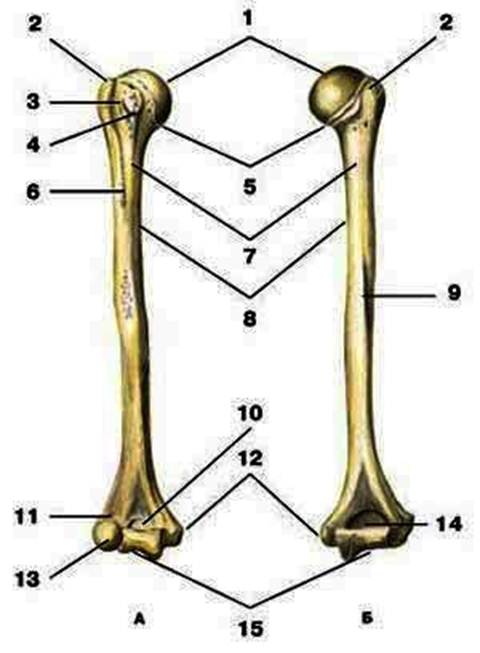

S: Цифра 1 обозначает головка плечевой кости.

S: Число 15 обозначает блок плечевой кости.

S: Цифра 5 указывает на хирургическая шейка плечевой кости.

S: Число 10 обозначает венечная ямка плечевой кости.

S: Число 14 указывает на локтевая ямка плечевой кости.

S: Цифра 9 указывает на борозда лучевого нерва плечевой кости.

S: Число 12 обозначает медиальный надмыщелок плечевой кости.

S: Стрелка указывает на большой бугорок плечевой кости.

S: Стрелка указывает на малый бугорок плечевой кости.